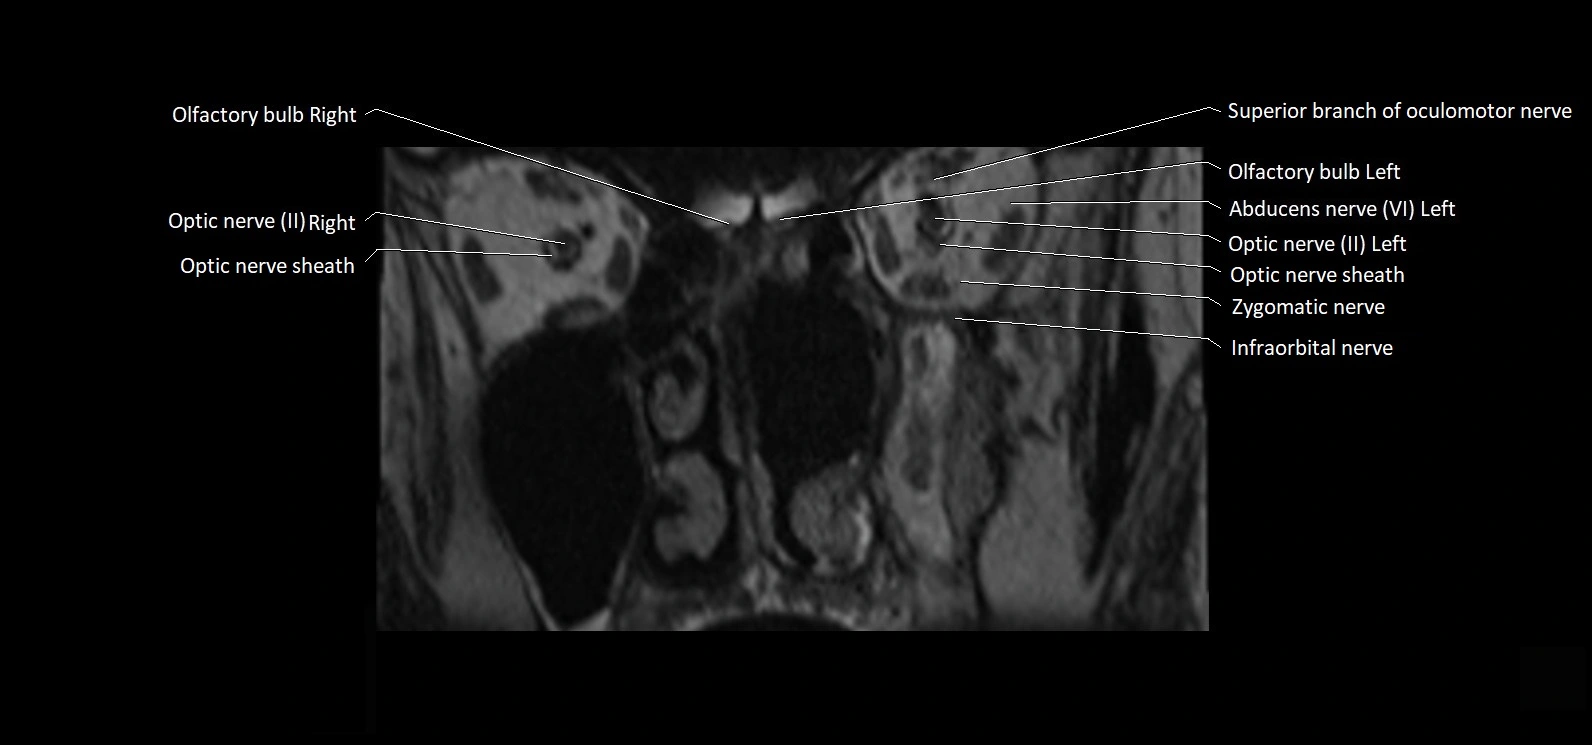

MRI Appearance

• The abducens nerve is a small, thin, linear structure

• Best visualized on high-resolution T2-weighted 3D MRI sequences (e.g., FIESTA or CISS)

• Seen as a hypointense (dark) line running from the brainstem at the pontomedullary junction, traversing the prepontine cistern, and entering Dorello’s canal under the petrosphenoidal ligament, then into the cavernous sinus, and finally the orbit

• May be challenging to visualize in standard MRI due to its small size

• Pathology may be inferred by absence, displacement, or enhancement of the nerve